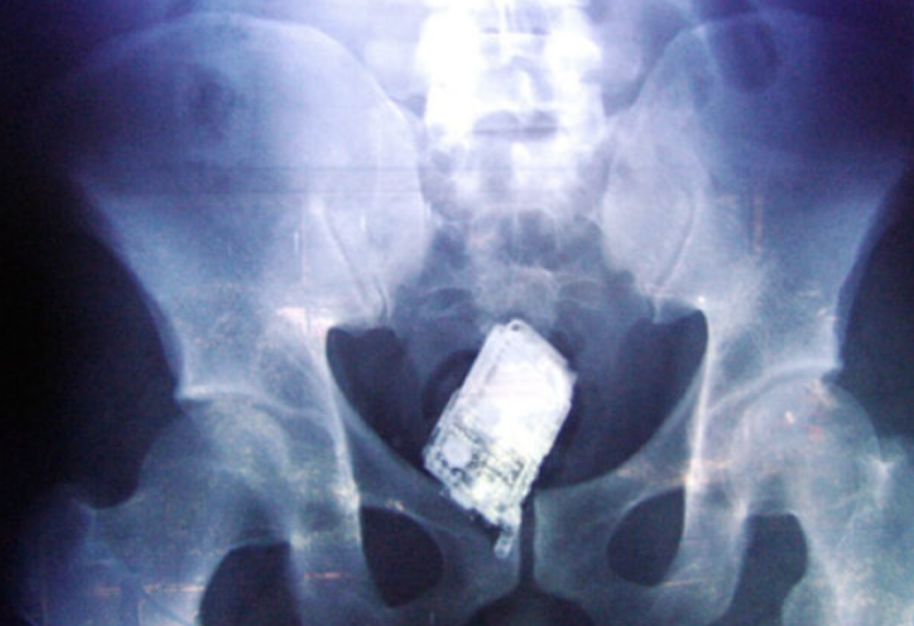

Мужчина обратился к врачам больницы с жалобами на боли в животе. В ходе осмотра медики сделали пациенту рентген и выяснили, что в желудке египтянина находится мобильный телефон.

Пациент признался, что проглотил его полгода назад, страдал от боли, но несмотря на все это не решался сходить к врачу. Он надеялся, что телефон органически выйдет из желудка, но этого не сучилось.

Телефон не давал нормально перевариваться пище — это приносило боль.